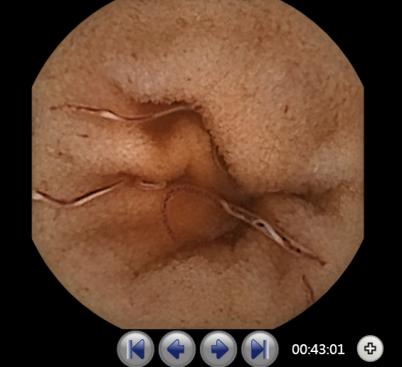

胶囊内镜下看见的小肠寄生虫肠道钩虫病是钩虫寄生人体小肠后所导致的

图片尺寸402x367